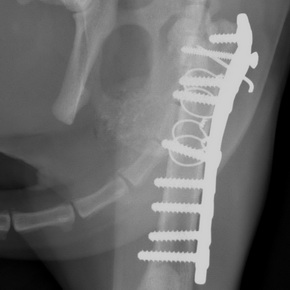

Orthopädie / Gelenkoperationen / Kreuzbandriß

Stationäre Behandlungen

Chirurgie / Bauch- und Brustkorboperationen